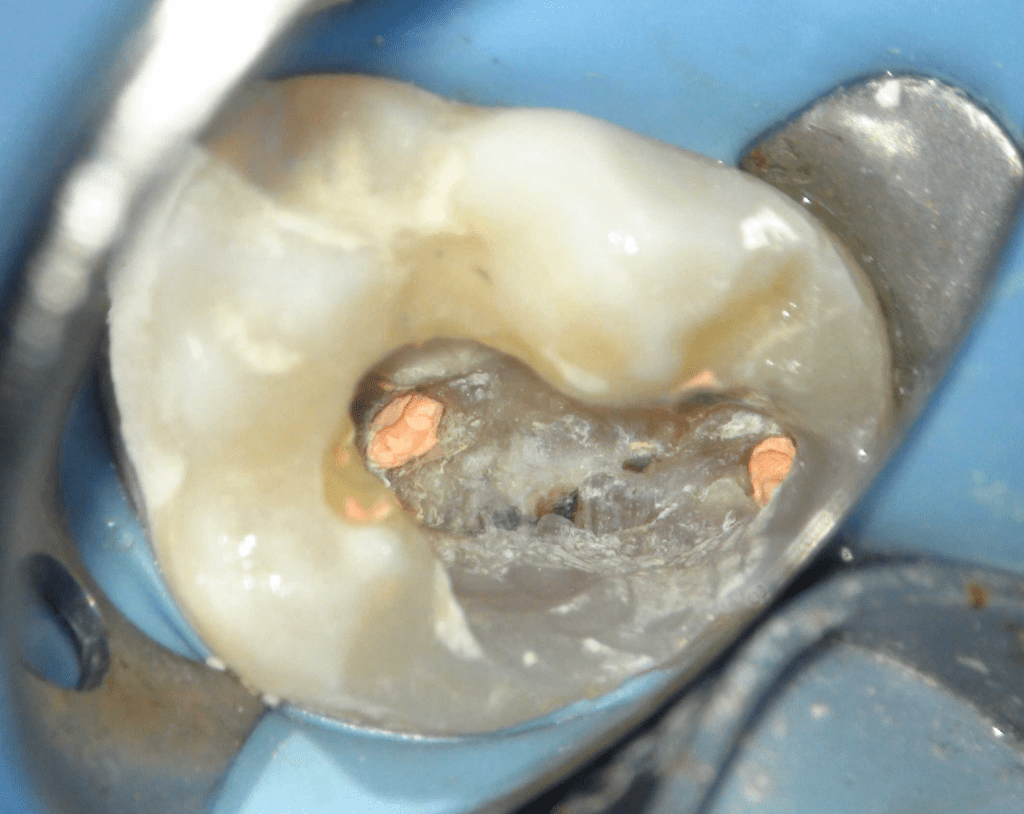

Pulpotomía biodentine + reco preendio